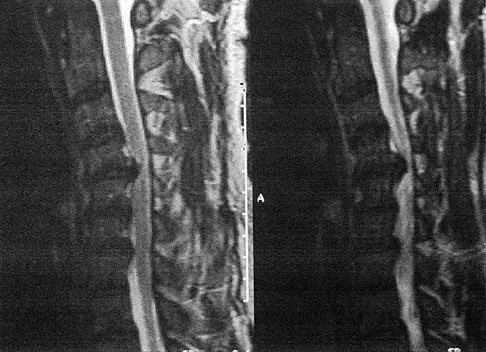

Question 48

An otherwise healthy 54-year-old man who underwent a successful multilevel lumbar decompression and fusion 4 years ago now reports increasingly severe bilateral thigh claudication with paresthesia and severe back pain for the past 12 months. Physical therapy, bracing, and epidural steroids have failed to provide relief. A radiograph and MRI scans are shown in Figures 15a through 15c. He is afebrile, and laboratory studies show an erythrocyte sedimentation rate of 5 mm/h and a normal WBC count. What is the best course of action?

Explanation